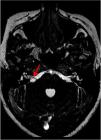

ResultsA total of 102 patients (63 women and 39 men) had vestibulocochlear involvement. The most common clinical indication was dizziness (41.18%). A unilateral vascular loop was found in 43 patients (right: 21.57%, left: 20.59%) and bilateral loops were found in 59 (57.84%) patients. The most common type of vascular loop was type II (right: 69.14%; left: 58.75%). The most common origin of vascular loops was the anterior inferior cerebellar artery (right: 66.67%, left: 65.00%). No associations were observed between vascular loops and sensorineural hearing, nystagmus, or vertigo. There was an association with tinnitus.

Resultados102 pacientes (63 mujeres y 39 hombres) presentaban afectación vestibulococlear. La indicación clínica más frecuente fue mareos (41,18%). Se halló asa vascular unilateral en 43 pacientes (derecho: 21,57%, izquierdo: 20,59%) y bilateral en 59 pacientes (57,84%). El tipo de asa vascular más frecuente fue el tipo II (derecho: 69,14%; izquierdo: 58,75%). El origen más frecuente fue la arteria cerebelosa anteroinferior (ACAI) (derecha: 66,67%, izquierda: 65,00%). No se observó ninguna asociación entre asas vasculares y pérdida de audición neurosensitiva, nistagmo o vértigo. Se halló una asociación con acúfenos.

The brainstem, situated in the posterior fossa, connects the brain to the spinal cord. Owing to its location, the nerves of the brainstem are closely related with vascular structures.